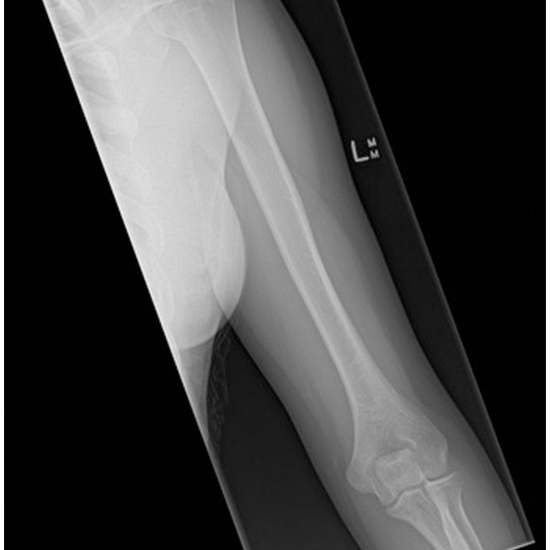

X-ray of the Humerus AP/Lateral View

Using an X-ray of the humerus, it is possible to show the bone in the upper arm (the humerus) and the soft tissues (skin and muscles) surrounding it.

• To determine whether or not the humerus (the bone of the upper arm) has been fractured and then to evaluate how well the bone is healing once it has been set.

• To diagnose any possible infections, osteoporosis, abnormalities, or abnormal growths of this bone.